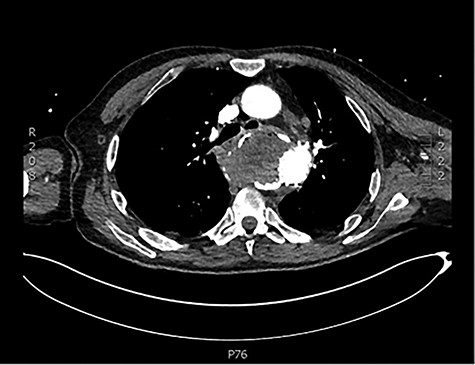

Initial basic investigations demonstrated a fall in his haemoglobin consistent with his history from 14 to 8 g/dl. Oesophago-gastro-duodenoscopy performed at the peripheral hospital was suggestive of a large Mallory–Weiss tear which was injected with adrenaline. Patient also underwent a computer tomography scan which demonstrated a large saccular aneurysm arising from the descending thoracic aorta adjacent to the oesophagus with secondary compression and displacement without any inflammatory or infective features (Fig. 1). CT aortogram did not demonstrate any contrast extravasation or blush into the oesophagus, but a fistula could not be excluded. Upon review of the imaging, it was decided that the patient should be transferred to our tertiary institution for further management with a probable diagnosis of aorto-oesophageal fistula.

CT scan demonstrating close relationship of oesophagus and aortic aneurysm sac.